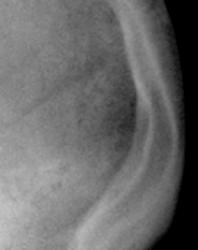

На иллюстрации 4 представлено «первично полученное» изображение черепа в боковой проекции. Снимок удовлетворительного качества, хорошо визуализируется «зона физиологического склероза» в. области лобно-теменного шва.

Иллюстрация 5 – произведена цифровая обработка изображения -  комментарии излишни.